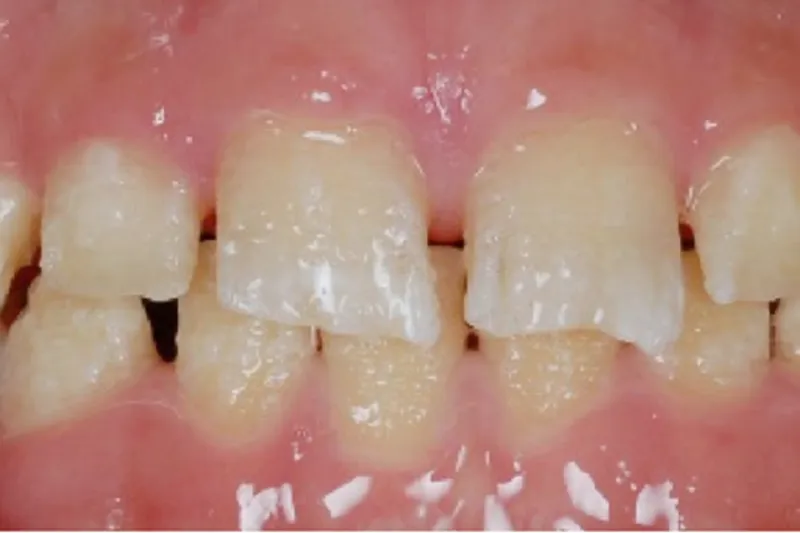

Keramisk protetisk behandling har varit förbehållet den vuxna populationen. Bristen på hållbar behandling under ungdomsåren för patienter med grava emaljstörningar har orsakat mycket lidande för patienter, frustration för terapeuter och höga kostnader för temporär tandvård. Patienter med amelogenesis imperfecta (AI) har dokumenterat stora problem under sin väntan på att kunna få en permanent terapi. Vi har använt nya keramiska material som ger bra hållfasthet även i tunna konstruktioner för att försöka lösa patienternas problem. Vi beskriver problematik och lösningsmöjligheter för patienter med grav AI. Genom våra studier som omfattar en retrospektiv utvärdering av rekommenderad vård, randomiserad klinisk studie (RCT) av keramisk kronterapi i unga år, studier på oral-hälsa relaterad livskvalitet, tandvårdsrädsla och inställning till tandvård samt djupintervjuer för att bättre förstå patienterna, har vi i en långtidsuppföljning kommit till slutsatsen att en tidig protetisk terapi med keramiska kronor kan rekommenderas i det unga permanenta bettet. Goda resultat uppmättes vad avser California Dental Association (CDA) kriterier för kvalitet, ”survival” och ”success”. Få biverkningar sågs och inga kronor lossade. Det är möjligt och kan rekommenderas att påbörja en fast protetisk rehabilitering med keramiska kronor på unga patienter redan under tonåren.

Keramisk protetisk behandling har varit förbehållet den vuxna populationen. Bristen på evidens för permanenta lösningar under ungdomsåren för patienter med grava emaljstörningar har orsakat mycket lidande, frustration för behandlande tandläkare och höga kostnader för temporär tandvård. Våra studier av patienter med amelogenesis imperfecta (AI) som omfattar en retrospektiv utvärdering av rekommenderad vård, randomiserade kontrollerade studier av keramisk kronterapi i unga år, studier på oral- hälsarelaterad livskvalitet, tandvårdsrädsla och inställning till tandvård samt djupintervjuer för patientförståelse, visar att tidig terapi med keramiska kronor kan rekommenderas i det unga permanenta bettet hos patienter med AI.